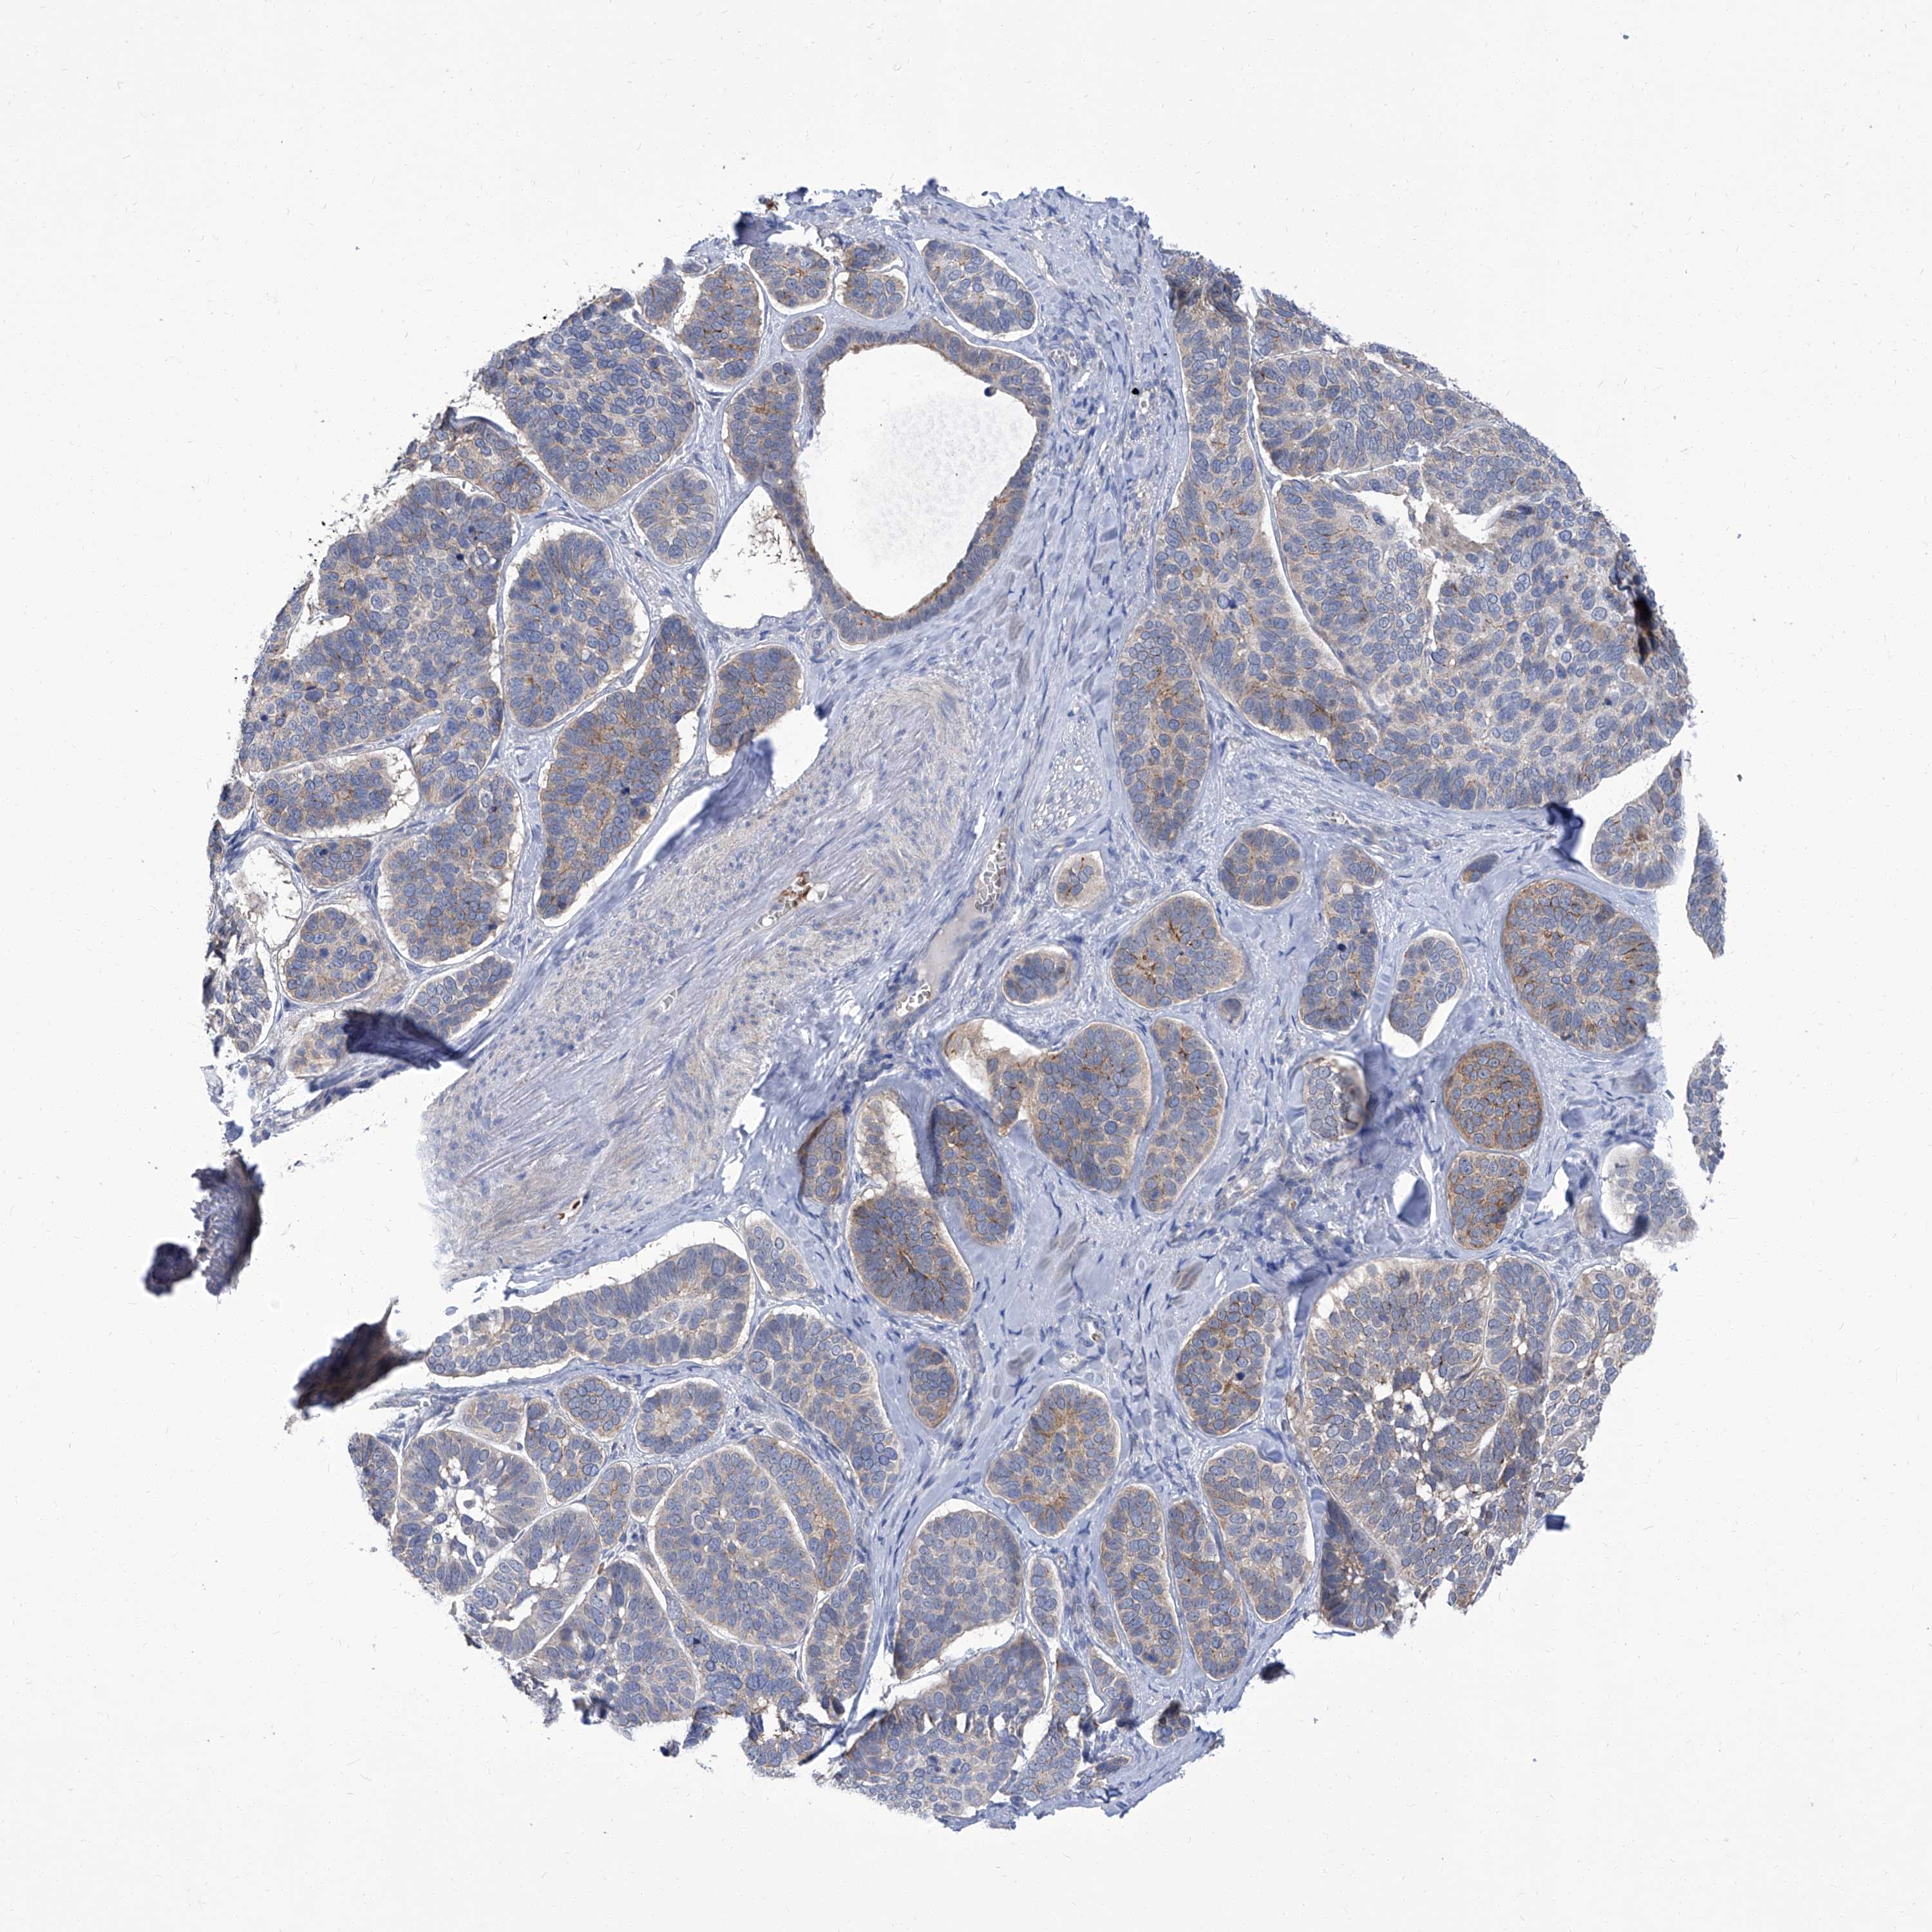

SKIN CANCER - Protein expressioni

A mouse-over function shows sample information and annotation data. Click on an image to view it in a full screen mode. Samples can be filtered based on level of antibody staining by selecting one or several of the following categories: high, medium, low and not detected. The assay and annotation is described here.

Each image is clickable and will lead to virtual microscopy that enables deeper exploration of all samples and also displays staining intensity scores, fraction scores and subcellular localization as well as patient and tissue information for each sample.

Antibody HPA030443

Staining

High

Medium

Low

Not detected

Intensity

Strong

Moderate

Weak

Negative

Quantity

>75%

75%-25%

<25%

None

Location

Nuclear

Cytoplasmic/membranous

Cytoplasmic/membranous,nuclear

Basal cell carcinoma

Squamous cell carcinoma, NOS

Squamous cell carcinoma, metastatic, NOS